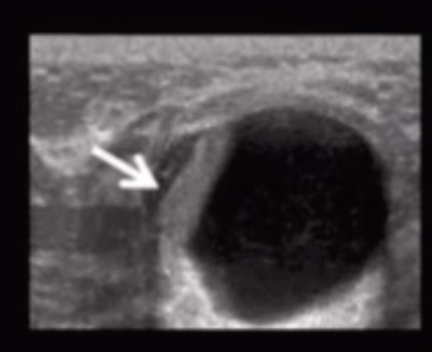

• Homogenously hypoechoic , well circumscribed mass on US